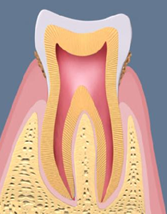

軽度歯周炎

歯肉炎が進行した状態です。3~4mm程度となった歯周ポケット内にプラークや歯石が溜まって炎症が強くなるため、歯ぐきの色が赤みを帯びてきます。歯を支える歯槽骨も吸収を始めます。